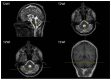

We report a case of SYNE1-associated autosomal recessive spinocerebellar ataxia (SCAR8) presenting with a complex multisystemic phenotype, including highly elevated creatine kinase levels and lower-leg muscle atrophy. In addition to identifying two novel pathogenic variants in the SYNE1 gene, whole-exome sequencing revealed three variants of uncertain significance in the DYSF gene. Electromyography and muscle magnetic resonance imaging indicated a neurogenic pattern of muscle involvement. These findings, along with the segregation analysis of the variants, allowed us to exclude DYSF-associated muscular dystrophy; however, we cannot entirely rule out the possibility that the DYSF gene variants may act as modifiers of the patient's phenotype.